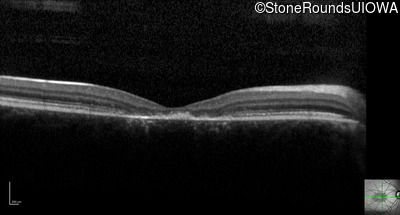

Optical Coherence Tomography - Right - 10/125 -1

Exemplar / OCT Stack

OCT Stack